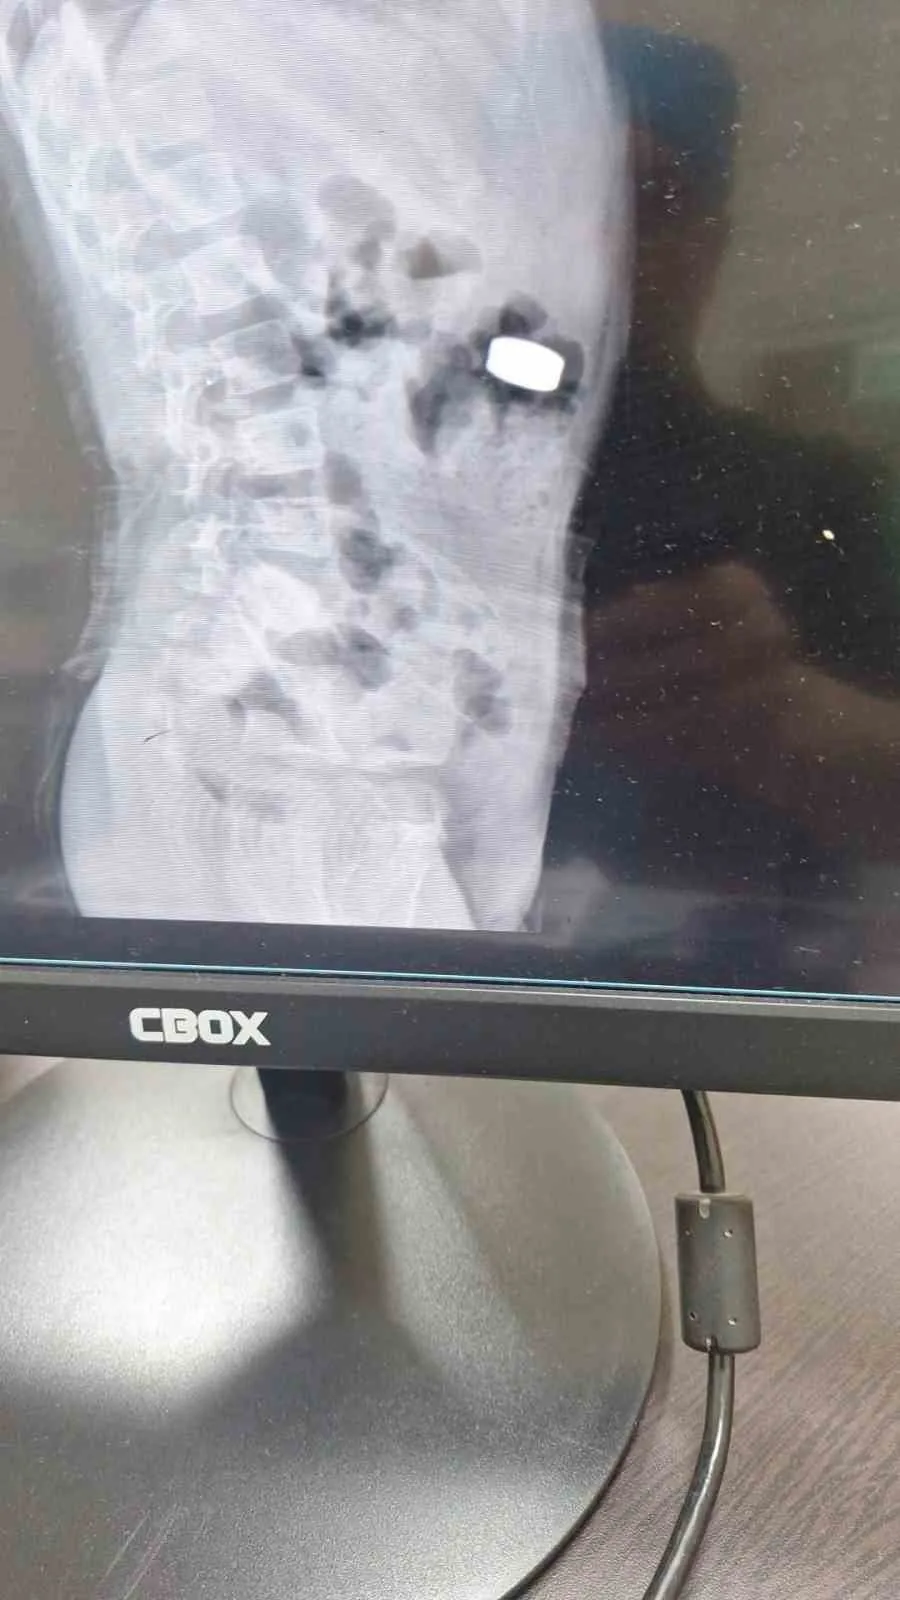

Karaman’da 4 yaşındaki İ.K.’nin mıknatıs yuttuğundan şüphelenen ailesi, Karaman Eğitim ve Araştırma Hastanesi Acil Servisi’ne başvurdu. Yapılan tetkiklerde çocuğun ince bağırsağında iki adet mıknatıs bulunduğu tespit edildi.

Gözlem altına alınan çocuğun sağlık durumu 5 gün boyunca takip edildi. Çocuk Cerrahisi Uzmanı Doç. Dr. Mehmet Uysal, takip süresince çekilen filmlerde mıknatısların yer değiştirmediğini belirtti.

Doç. Dr. Mehmet Uysal, hastanın genel anestezi altında ameliyata alındığını ifade ederek, “İnce bağırsakta iki mıknatısın birbirine yapışık halde olduğunu gördük. Gerçekleştirdiğimiz operasyonla mıknatısları çıkardık. Ameliyat sonrası hastamız üçüncü gününde taburcu edildi. Şu an genel durumu iyi” dedi.